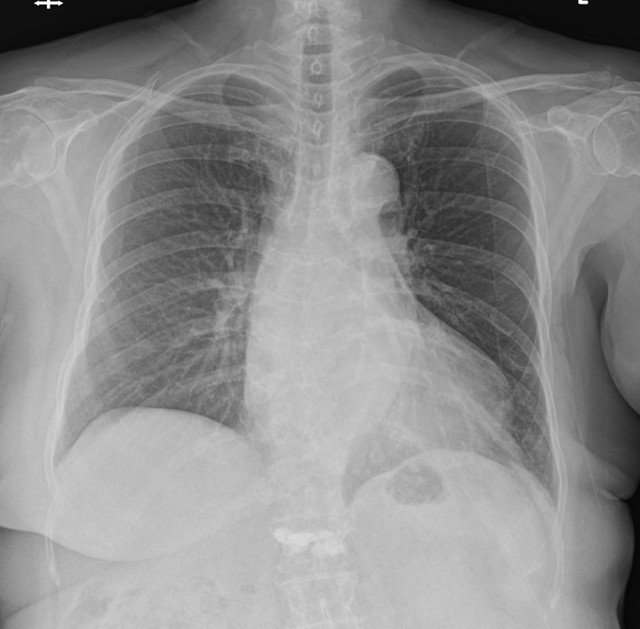

This is a 70 years old female with Hypertension, Diabetes Mellitus, Dyslipidemia, and 3-vessel-disease post LAD and LCX stenting at a local hospital.She got angina deterioration in recent 3 months and received coronary angiography in the local facility. After that, the patient was refered to our center for balloon un-dilatable Severe In-Stent Restenosis.

The patient's echocardiography showed the LVEF 68% with apical anteroseptal hypokinesia.

The RCA was calcified but no significantly severe stenosis.The LCX was calcified with mild stenotic lesion and a patent old stent.The LAD was severely calcified with an under-expanded old stent at middle to distal part. The lesion was also severely stenotic. The proximal to middle LAD had moderately stenotic lesion with calcification also.